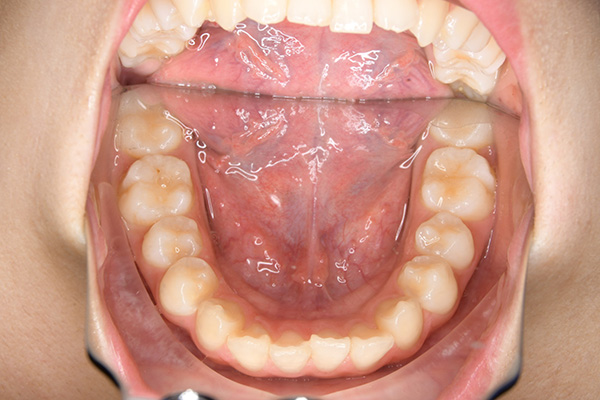

初診時

FP・IOP

口腔内所見 over jet 7.5mm,over bite 3.5mm,大臼歯関係はⅡ級 。Hellmanのdental ageはⅢAであり上突咬合を呈していた。